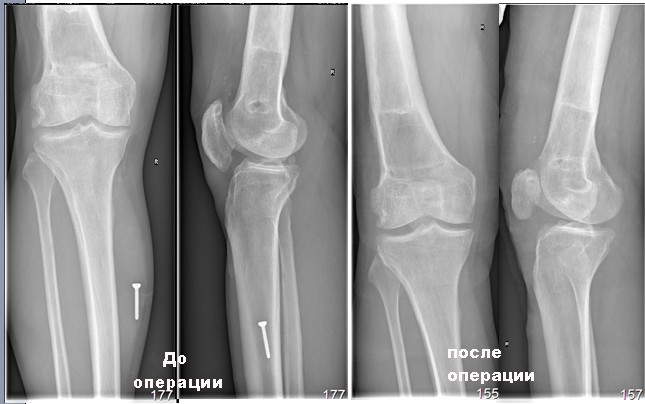

Пациент, мужчина, 45 лет. В 1982 году получил закрытый перелом диафиза бедренной кости справа. Результат консервативного лечения-варусная деформация бедренной кости В 1987 году выполнена вальгусная корригирующая остеотомия на уровне дистального эпифиза бедренной кости: варус бедренной кости нивелирован. Но в процессе лечения сформировалась выраженная контрактура в правом коленном суставе. Производилось 2 раза агрессивная разработка правого коленного сустава в аппарате типа Илизарова. В настоящее время беспокоят боли в области правого надколенника, при длительной ходьбе появляется ощущение скованности в 4-х главой мышце бедра, при отрыве правой стопы, голень и стопа как бы выбрасывается вперед (пациент, при этом, процесс разгибания в коленном суставе плохо контролирует). Правый коленный сустав внешне не деформирован, не отечен. Объем движений: сгибание до 90 градусов (до прямого угла, разгибание полное_180 гр. Сустав стабилен во всех плоскостях. Надколенник расположен практически на уровне суставной щели (тибиа-феморальной), малоподвижен, так называемая «игра надколенника» у пациента резко снижена . Пациент поступил в наше отделение для выполнения операции в объеме эндопротезирования правого коленного сустава. Однако, оценив коленный сустав, мы засомневались в необходимости данной операции этому пациенту. В данном случае , низкое стояние дегенеративно измененного правого надколенника нарушает функцию разгибательного аппарата правого коленного сустава и основная причина сосредоточена здесь, в надколеннике (по нашему мнению). У меня вопрос к коллегам: как деликатно, на нарушая разгибательный аппарат, помочь пациенту? Какие виды реконструктивных операции предпочтительны. С уважением Шушания Батал, ФБУ 3 ЦВКГ имени А А Вишневского

винт, видимый на рентгенснимках, фиксирован к коже пациента лейкопластырем при рентгенографии рентгенлабарантом, используется для калибровки рентегнснимка при планировании операции эндопротезирования.

спешу поделиться результатом операции, проведенной 25/01/2012 года. Выполнен передний срединный доступ к коленному суставу длиной до 8 см, полость коленного сустава вскрыта медиально от надколенника, выделилось до 20 мл синовиальной жидкости. Надколенник вывернут. Суставная поверхность надколенника склерозирована,

резко слерозирован (до каменной плотности) верхне-наружный квадрант наколенника. Хрящ на надколеннике практически отсутствовал. Остеофиты по всей окружности надколенника (надколенник имел вид "блюдца" из-за этих сотеофитов). Жировое тело гипртрофировано. Хрящ на мыщелках бедра достаточно сохранный, хотя не идеальный. В межмыщелковом простарнстве бедра (спереди крестообразных связок)остефиты.

До операции мы еще советовались с Александром Каземирским из РНИИТО им Р.Р.Вредена. Он советовал нам выполнить " реконструктивно-пластическую

операцию по артропластике переднего отдела коленного сустава: моделирующая резекция нижнего полюса надколенника для уменьшения его вертикального размера и уменьшения гиперпрессии на фасетку бедренной кости. Придать надколеннику сесамовидную форму и борозде - соответствующее углубление." Мы практически выполнили все то, что нам рекомендовал А. Каземирский.

Сегодня объем движений: сгибание 60 градусов, разгибание 180. Конечно, движения в коленом суставе пока болезненны, особенно в области резецированного дистального полюса надколенника. Будем следить за реабилитацией данного пациента.

Прилагаю картинки до и после.